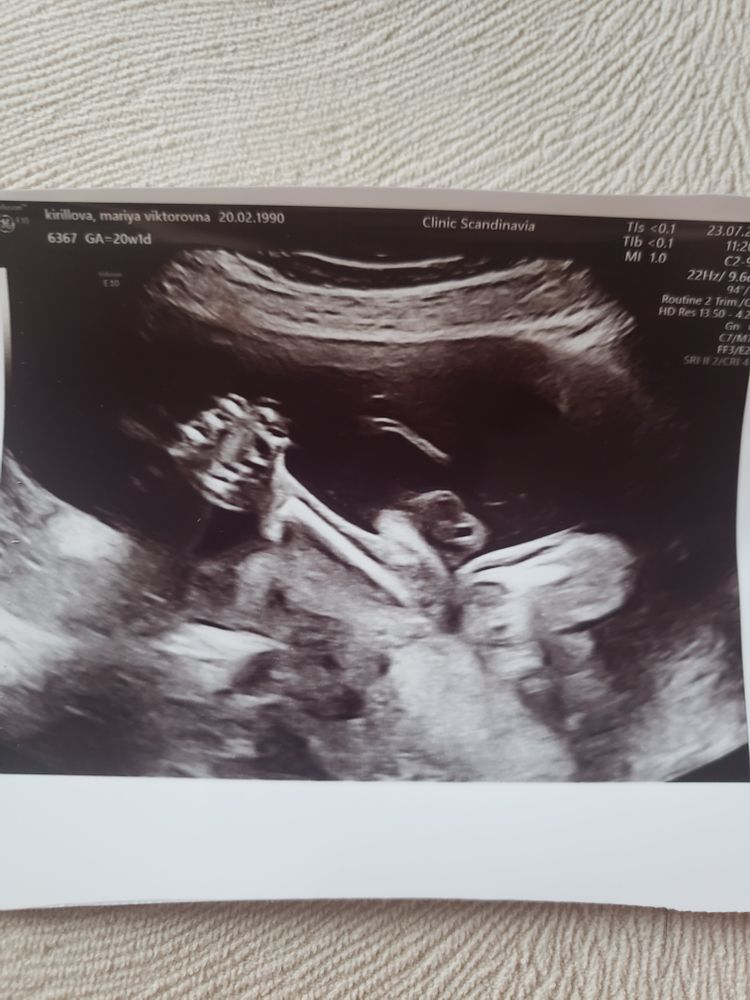

На момент скрининга срок 20+1, полет нормальный. Подтвердили девушку. И если свои гениталии она показывала охотно, то лицо скрывала до конца, одни кулаки в экран. Дали в конце 2 фотки 3д. Все бережно собирается для альбомчика (ещё бы найти, который понравится). Вещей пока особо не покупала, почему то теперь думаю, что сделаю все в декрете, и что 10 примерно недель мне хватит.

А это Антонина Денисовна показала всем оберег от сглаза (это кулак, а то дома не поняли что это такое)